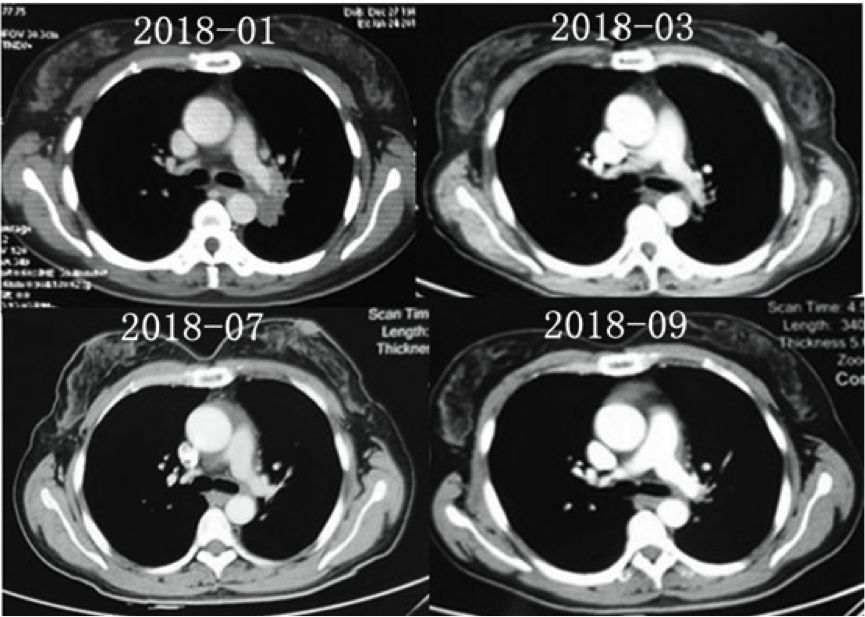

患者诊断IVA期伴ALK阳性,故于2018年2月开始克唑替尼治疗,治疗过程耐受性良好,疗效评价PR。并且患者于2018年9月因腰骶部疼痛行骶骨转移灶放疗。

图4.患者接受克唑替尼治疗时候的基线情况(2018-01)、以及治疗随访胸部CT影像

2018年9月29日,患者病情出现恶化,出现头痛伴短暂性意识障碍,查体双侧瞳孔等大等圆,对光反射灵敏,心率45次/分,血压160/100mmHg,考虑颅内高压导致出现Cushing反应。立即予以镇静、脱水等对症处理,并紧急腰穿行脑脊液引流,同时鞘内注射培美曲塞化疗联合全身培美曲塞单药化疗。患者于2018年9月30日恢复意识,并能交流顺畅,活动自如。同日,患者开始口服靶向阿来替尼二线治疗,并于10月2日因头痛再次腔内注射培美曲塞单药化疗。后患者肺部和中枢神经系统控制可,患者PS评分恢复0分。从治疗的结局来看,该病例算是一例非常成功的脑膜转移治疗成功的病例。